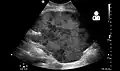

Imaging

Postoperatively, kidneys are periodically assessed by ultrasound to assess for the imaging and physiologic changes that accompany transplant rejection. Imaging also allows evaluation of supportive structures such as the anastomosed transplant artery, vein, and ureter, to ensure they are stable in appearance.

The major sonographic scale in quantitative ultrasound assessment is with a multipoint assessment of the resistive index (RI), beginning at the main renal artery and vein and ending at the arcuate vessels. It is calculated as follows:

- RI = (peak systolic velocity – end diastolic velocity ) / peak systolic velocity

The normal value is ≈ 0.60, with 0.70 being the upper limit of normal.[69][70]

Postoperative bleeding following kidney transplant as seen on ultrasound[86]